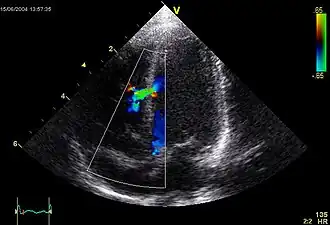

![]() Эхокардиографическое изображение дефекта межелудочковой перегородки в мышечной части. | |

В межжелудочковой перегородке выделяют 3 отдела: верхняя часть — мембранозная, прилегает к центральному фиброзному телу, средняя часть — мышечная, и нижняя — трабекулярная. Соответственно этим отделам называют и дефекты межжелудочковой перегородки, однако большинство из них имеют перимембранозную локализацию (до 80 %). На долю мышечных ДМЖП приходится 20 %[3][5].

При доплер-ЭхоКГ уточняется место расположения дефекта, его размер, определяется давление в правом желудочке и лёгочной артерии. В первой стадии лёгочной гипертензии давление в ПЖ не превышает 30 мм.рт.ст., во второй стадии — от 30 до 70 мм.рт.ст., в третьей — более 70 мм.рт.ст.[6]